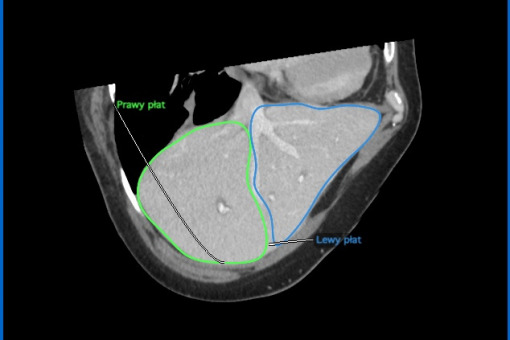

Zielona i niebieska linia pokazuje prawy i lewy płat przeszczepianej wątroby, jej podział (źródło WUM)

Operacja polegała na podziale na dwie części narządu pobranego od zmarłego dawcy i przeszczepieniu prawej części wątroby dla jednego biorcy i lewej części wątroby dla drugiego biorcy – poinformował PAP rzecznik prasowy WUM Jarosław Kulczycki.